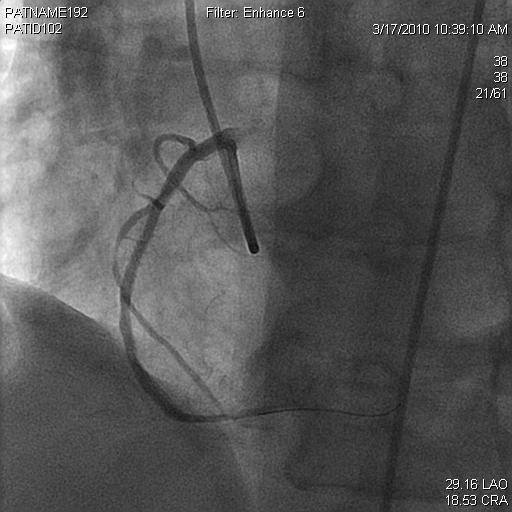

Sinus arrest rarely occurs during acute myocardial infarction involving the right coronary artery (RCA) and sinus node (SN) artery. We report a rare case of sinus arrest caused by SN artery occlusion following RCA stenting. A 56-year-old woman with a significant history of RCA stenosis with prior bare metal stenting, presented to the emergency department with anginal chest pain. Initial work up showed significant elevation of cardiac troponin T with T-wave inversion in the inferior leads on electrocardiogram (ECG). Coronary angiography revealed a 90% stenosis of midportion of the RCA, mild occlusion in the left anterior descending coronary and left circumflex coronary arteries. Stenting was performed on the RCA lesion. Immediately after undergoing those interventions, thrombosis developed and occluded SN artery. Electrocardiogram showed junctional escape rhythm without P waves at a heart rate of 30 beats per minute, suggesting sinus arrest. The clot in the SN artery was identified and thrombectomy was performed. Neither symptoms nor hypotension were identified during this arrhythmia. Six days later, normal sinus rhythm began to appear on EKG with improving heart rate, and patient still remained completely hemodynamically stable. Pre-discharge exercise stress test had shown 50% predicted heart rate without ST segment change. Sinus node dysfunction is commonly related to degenerative processes, and rarely caused by thrombosis in the SN artery. In our case, we emphasize the potential complication of sinus arrest after RCA stent implantation.

窦性停搏在累及右冠状动脉(RCA)和窦房结(SN)动脉的急性心肌梗死期间很少发生。我们报告一例RCA支架置入术后因SN动脉闭塞导致窦性停搏的罕见病例。一名56岁女性,有RCA狭窄及既往裸金属支架置入史,因心绞痛胸痛就诊于急诊科。初始检查显示心肌肌钙蛋白T显著升高,心电图(ECG)下壁导联T波倒置。冠状动脉造影显示RCA中段90%狭窄,左前降支冠状动脉和左旋支冠状动脉轻度闭塞。对RCA病变进行了支架置入。在进行这些干预后立即发生血栓形成并闭塞了SN动脉。心电图显示交界性逸搏心律,无P波,心率为每分钟30次,提示窦性停搏。识别出SN动脉内的血栓并进行了血栓切除术。在这种心律失常期间未发现症状或低血压。6天后,心电图开始出现正常窦性心律,心率改善,患者血流动力学仍完全稳定。出院前运动负荷试验显示心率为预测值的50%,无ST段改变。窦房结功能障碍通常与退行性病变有关,很少由SN动脉血栓形成引起。在我们的病例中,我们强调了RCA支架植入术后窦性停搏的潜在并发症。